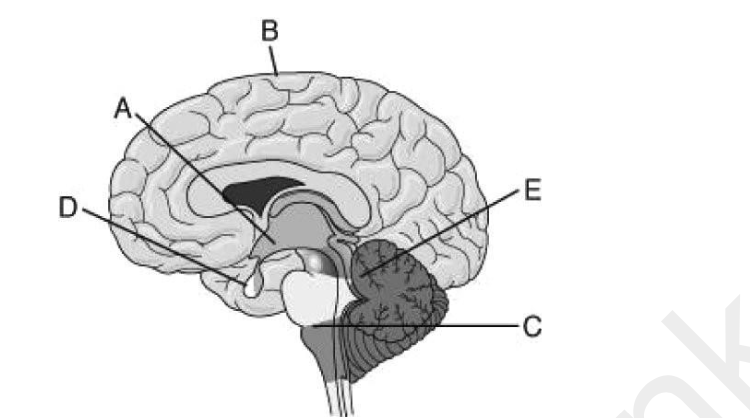

39) Use the figure to answer the following question.

If a person suffered a serious blow to the head that resulted in damage to the outer layer of brain

region B, what might be the expected outcome?

A) The person would be unable to breathe.

B) The person's perception, voluntary movement, and/or learning would be impaired.

C) The person would not be able to detect any light in the environment.

D) Emotional responses would be impaired.

B